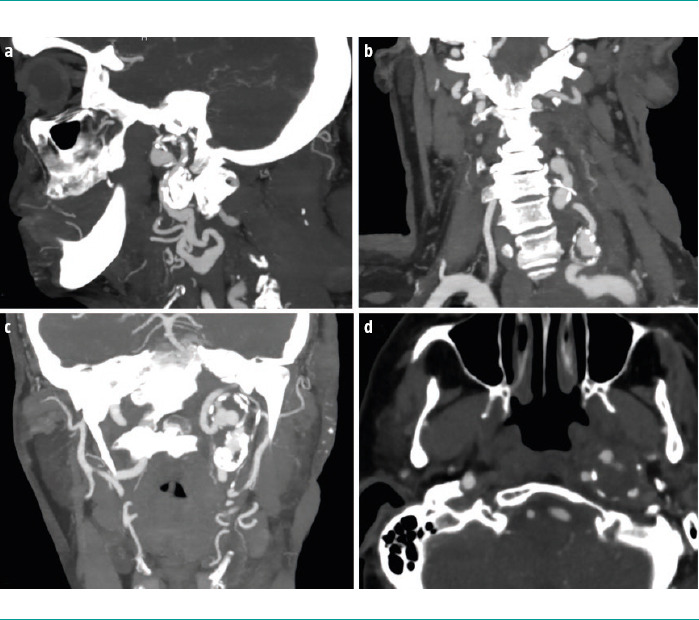

Case report: A 67-year-old woman with a genetic diagnosis of NF1 and a history of multiple exeresis of neurofibromas in the left cervical region. The patient presented with a painful flare-up and swelling in the region. A cervical magnetic resonance imaging was performed, which showed signs of plexiform neurinoma growth and a lesion suggestive of aneurysm in the left cervical internal carotid artery. A subsequent computed tomographic angiography confirmed the presence of a thrombosed aneurysm with associated critical stenosis, and identified three additional aneurysms in the proximal left vertebral artery. Given the asymptomatic presentation and adequate haemodynamic compensation, the patient was prescribed a conservative treatment and clinicoradiological follow-up.